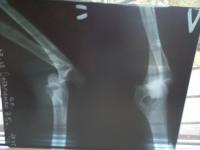

--~0.jpg

колено и рельса.Просмотров: 1791Комментариев: 15 руль